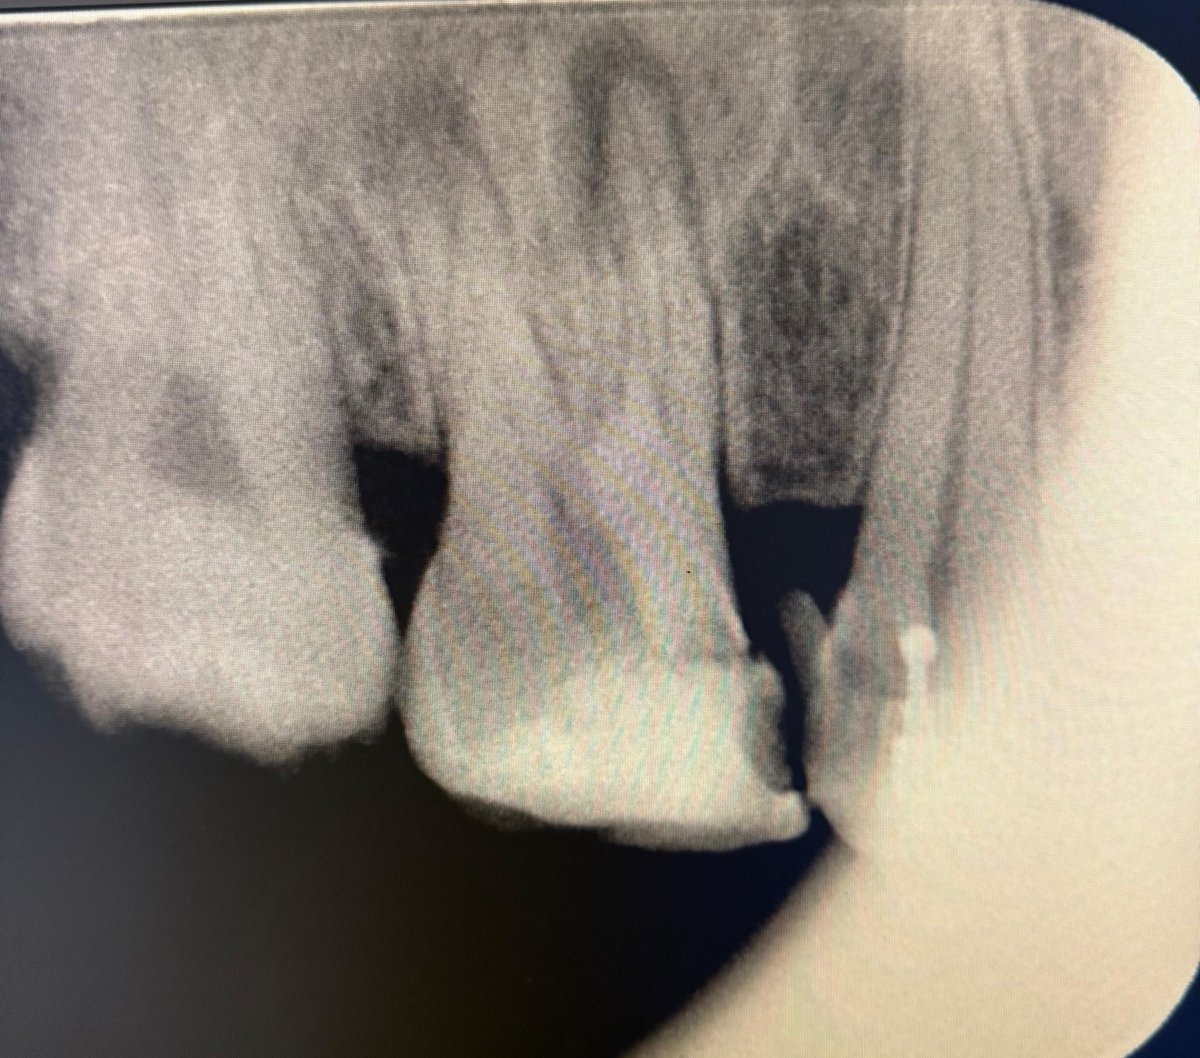

حالة جميلة لصباح اليوم 🙏🏻

Root Canal Treatment #34

Dx:SIP+SAP

Gingival overgrowth and deep caries in the distal wall, Rebuild the distal wall to achieve optimum isolation ✨

Next Step: Crown